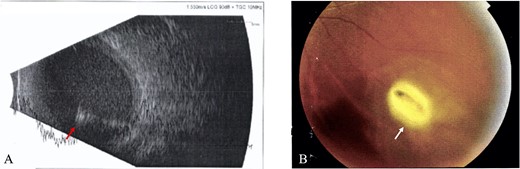

All IOFBs were successfully identified using slit-lamp biomicroscopy, fundus examination, B-scan ultrasonography, plain orbital X-ray, and viewed intraoperatively. Most foreign bodies were intravitreal (four patients, Fig. 1), followed by intraretinal (two patients, Fig. 2), intralenticular (two patients, Fig. 3) and intracorneal (one patient, Fig. 4).

Intralenticular foreign body; (A) B-scan ultrasound confirmed lens opacity, intact posterior capsule and suspected lenticular IOFB (red arrow), with normal vitreous and retina of the RE (Case 5), (B) Slit lamp bio-microscopy revealed corneal rupture and iris prolapse (Zone I) at 2 o’clock limbal, flat AC and traumatic cataract on the RE, (C) corneal rupture (Zone I) at 9 o’clock paracentral, shallow AC and traumatic cataract on the LE were discovered in Case 8 (yellow arrow).